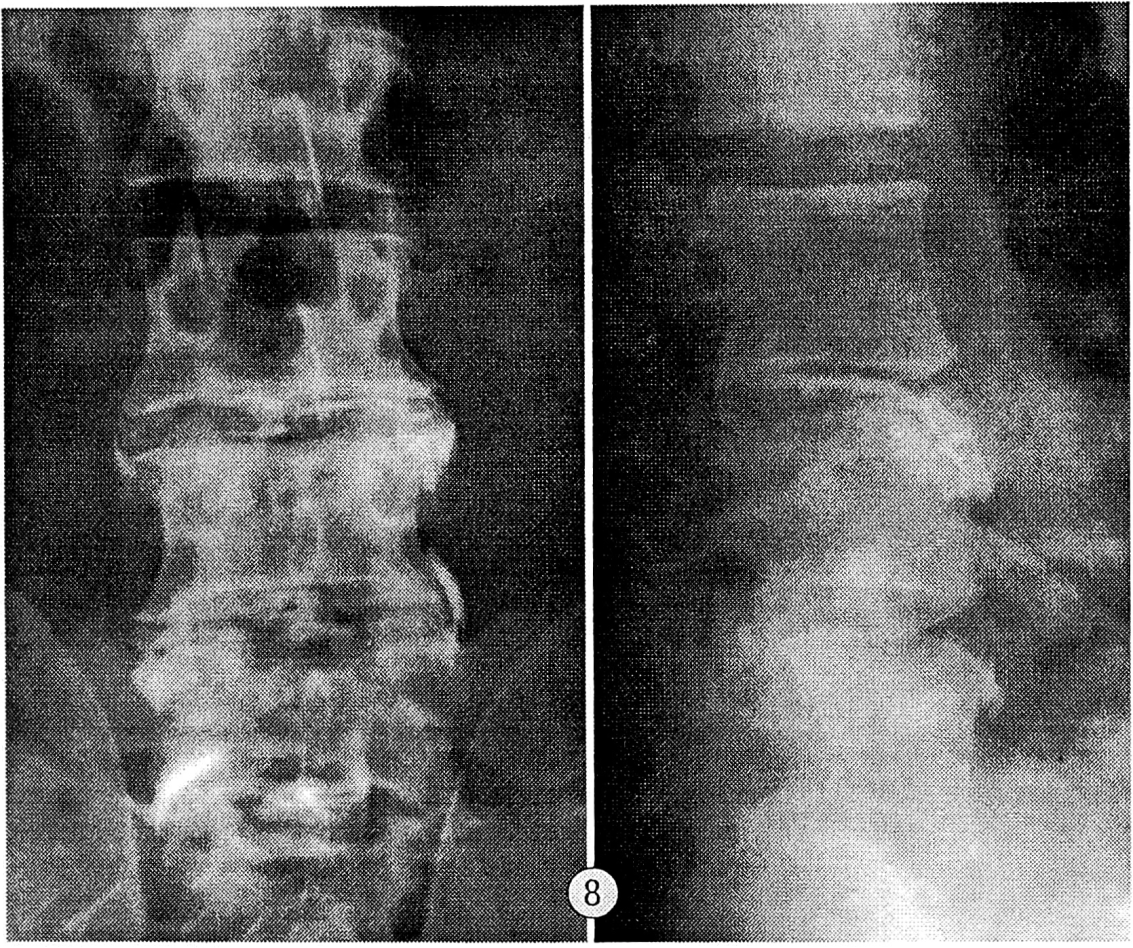

Внеламинарный тип дискограмм наблюдался в сегментах, где имело место отделение переднего апофиза от тела позвонка, и характеризовался выпадением студенистого ядра диска между несросшимся передневерхним апофизом и передневерхним углом тела позвонка. Нуклеарная тень представляла собой протянувшуюся вдоль краниальной поверхности тела позвонка гомогенную полосу шириной 2— 3 мм. В 8 случаях отмечалось контрастирование фрагментов фиброзного кольца. Высота межтелового промежутка оказалась сниженной практически на всех дискограммах (см. рис. 8). Емкость диска составляла не менее 1,5—1,8 мл; введение контрастного вещества не сопровождалось появлением боли.

Рис. 8. Внеламинарный тип дискограмм сегментах L3—4, L4—5.